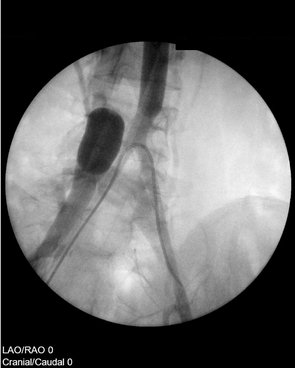

Die isolierte Extremitätenperfusion wurde als erweiterte isolierte Extremitäten-Stop-Flow-Infusion (EISLI) durchgeführt, bei der das Becken in das Perfusionsbett mit einbezogen wurde. Ballonkatheter wurden in der arteriellen und venösen Bifurkation im Becken eingeführt. Zur Erhöhung der Wirkstoffkonzentration an der Tumorstelle wurde ein arterieller Angiographiekatheter mit der Spitze direkt vor der Tumorregion platziert. Vor Beginn der Perfusionsphase erfolgte eine Wirkstoffexposition während einer Stop-Flow-Phase.

Die genauen Details zur Infusionsmethodik (Abb. 2), der Art und Dosierung der angewandten Chemotherapeutika und den Behandlungszyklen sind der Originalstudie zu entnehmen. Im Anschluss an vier Zyklen EISLI erfolgte die operative Entfernung des Tumors und die Implantation einer Kniegelenk-Endoprothese in einem externen orthopädischen Zentrum, sowie zwei Monate später ein weiterer adjuvanter EISLI-Zyklus.

Röntgenaufnahme einer Stop-Flow-Infusion im Rahmen der EISLI-Methode zur regionalen Chemotherapie eines Osteosarkoms am Femur.

Abb. 2: Infusionsmethodik der EISLI-Methode